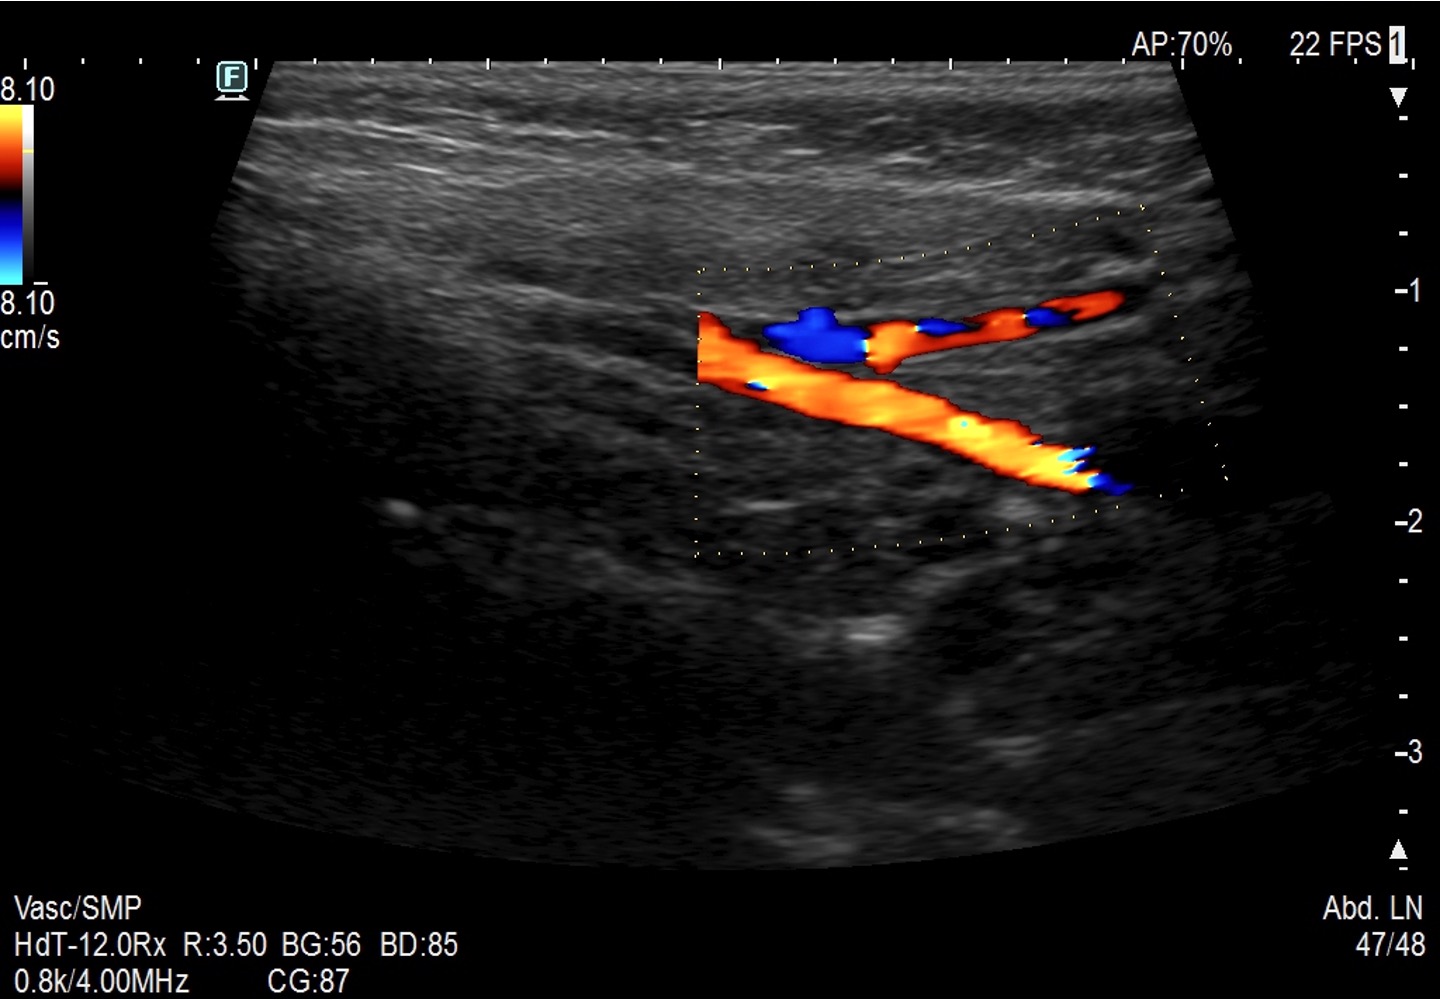

W USG ślinianki charakteryzują się echogenicznością wyższą od echogeniczności mięśni (zbliżoną do echogeniczności tkanki tłuszczowej oraz echogeniczności prawidłowego miąższu tarczycy) i jednorodną echostrukturą. W warunkach prawidłowych przewody wyprowadzające zazwyczaj są niewidoczne. Echogeniczność ślinianki podżuchwowej może być nieco niższa od echogeniczności ślinianki przyusznej. Unaczynienie prawidłowych ślinianek jest skąpe, a w przypadku ślinianek podjęzykowych często trudne do uwidocznienia.

Integralną częścią oceny ślinianek jest ocena węzłów chłonnych szyjnych. O tym, jak ocenić węzły chłonne szyjne u dziecka, możesz posłuchać w tym wykładzie.